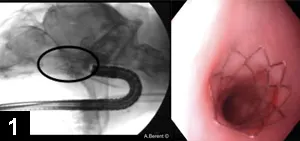

Figure 4. Endoscopic retrograde cholangiopancreatography in a canine patient during common bile duct stent placement

The major duodenal papilla can be visualized using a side-view duodenoscope and cannulated with a sphincterotome catheter. A guide wire can be advanced into the common bile duct under fluoroscopic guidance after retrograde cholangiogram–pancreatogram; a polyurethane or metallic stent is advanced over the wire into the common bile duct via endoscopy–fluoroscopy, transverses the major duodenal papilla, and exits into the duodenum. This stent can be in place until the obstructive lesion resolves (eg, for pancreatitis) or as a permanent treatment for strictures or neoplasia. This approach bypasses the need for rerouting biliary surgery for extrahepatic biliary obstructions (Figure 4).